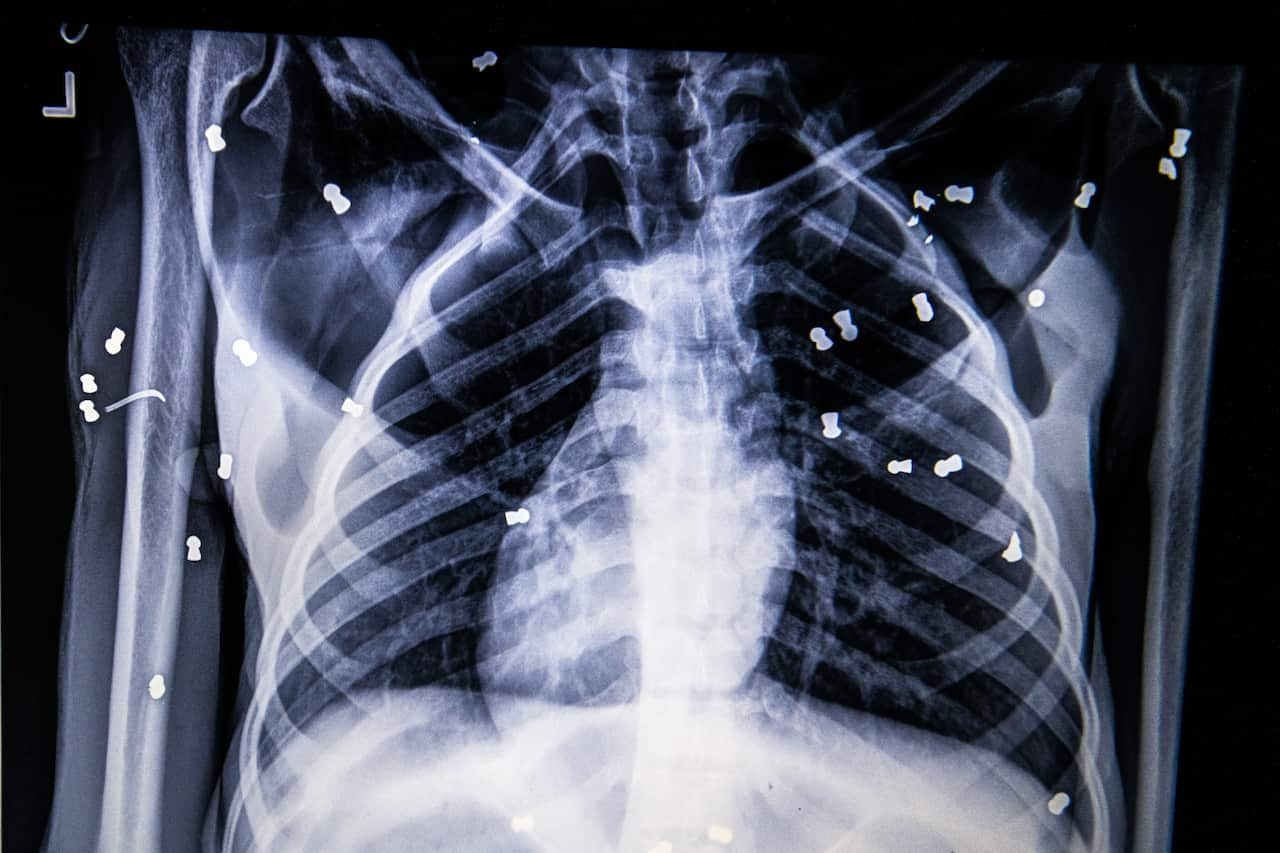

An X-ray showing air-rifle pellets inside Hope, the orangutan, outside the city of Medan, Indonesia. Source: The New York Times

By the end, Hope’s torso was slashed with deep lacerations. Multiple bones were broken. Seventy-four pellets were lodged in her body. Her months-old baby had been ripped away.